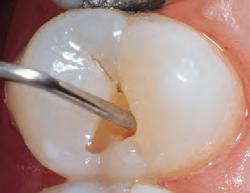

Sable Seek caries indicator contains FD&C dyes, and Seek caries indicator contains D&C dyes in a glycol base. Both are used to stain carious and demineralized dentin.

Seek and Sable Seek caries indicators stain carious and demineralized dentin and can be very useful for difficult-to-see areas, for example; undercuts of preparations, dark dentin, areas along the DE junction, etc. Green Sable Seek caries indicator helps visualization of decay in deep caries cases to help avoid pulp exposures.

PROCEDURE

dentin) with slow-speed round bur or excavator. To control overexcavating near the pulp, remove final portion of caries with hand excavator.